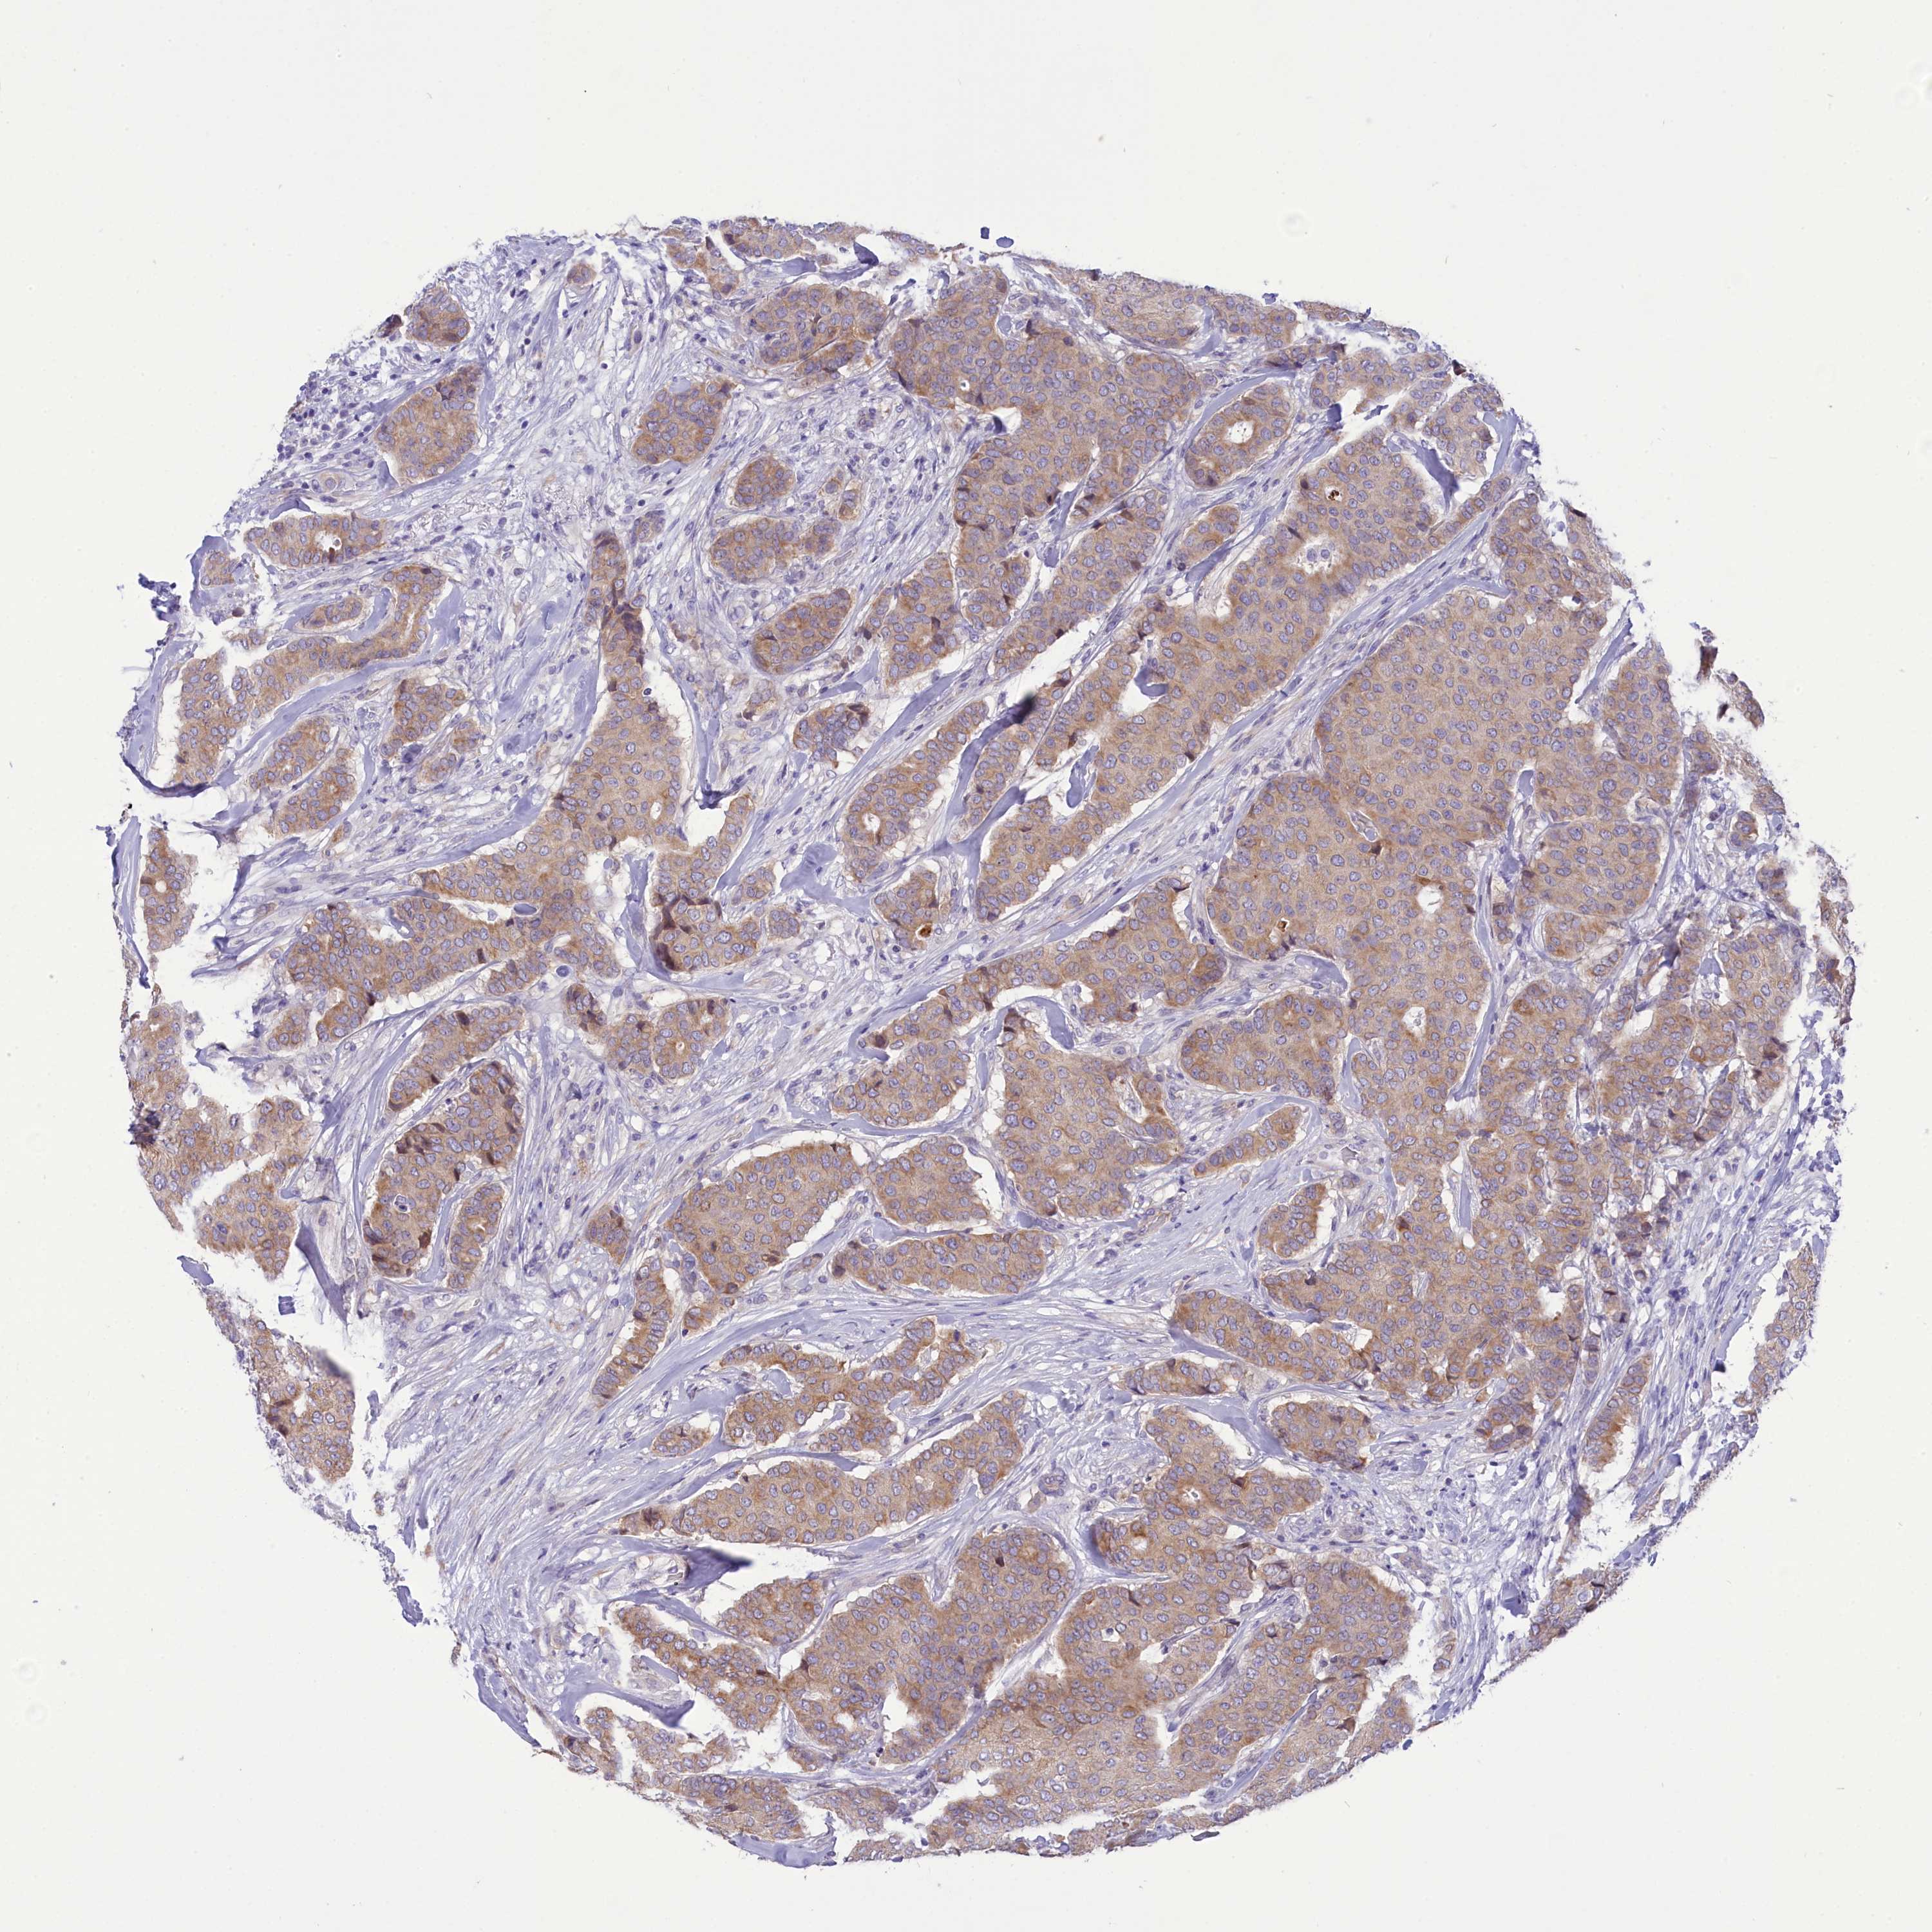

BRCA TCGA BRCA VALIDATION PROTEIN EXPRESSION